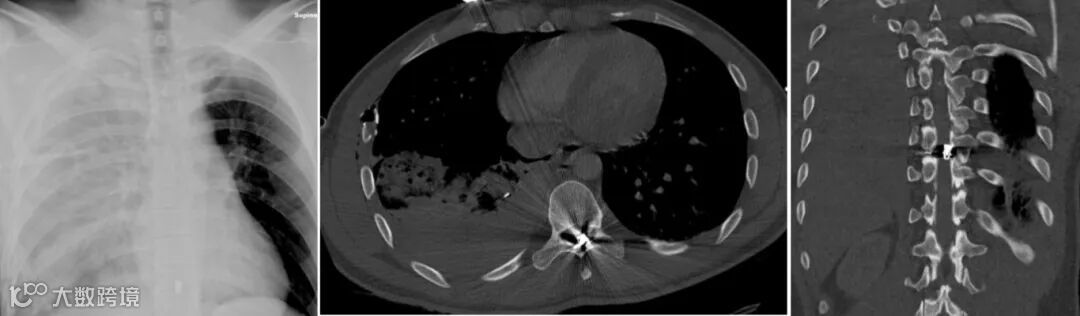

男,17岁,右侧胸腔遭枪击后,右侧胸部高密度子弹碎片,右胸腔中度血气胸,海姆立克瓣膜胸腔引流术后,伴有皮下气肿,纵隔左移。

CT扫描可精准评估肺损伤、心血管损伤及定位异物:

肺挫伤:弹道周围斑片状磨玻璃影,边界模糊;

肺裂伤:表现为含气或含血的囊腔,可伴血气胸。